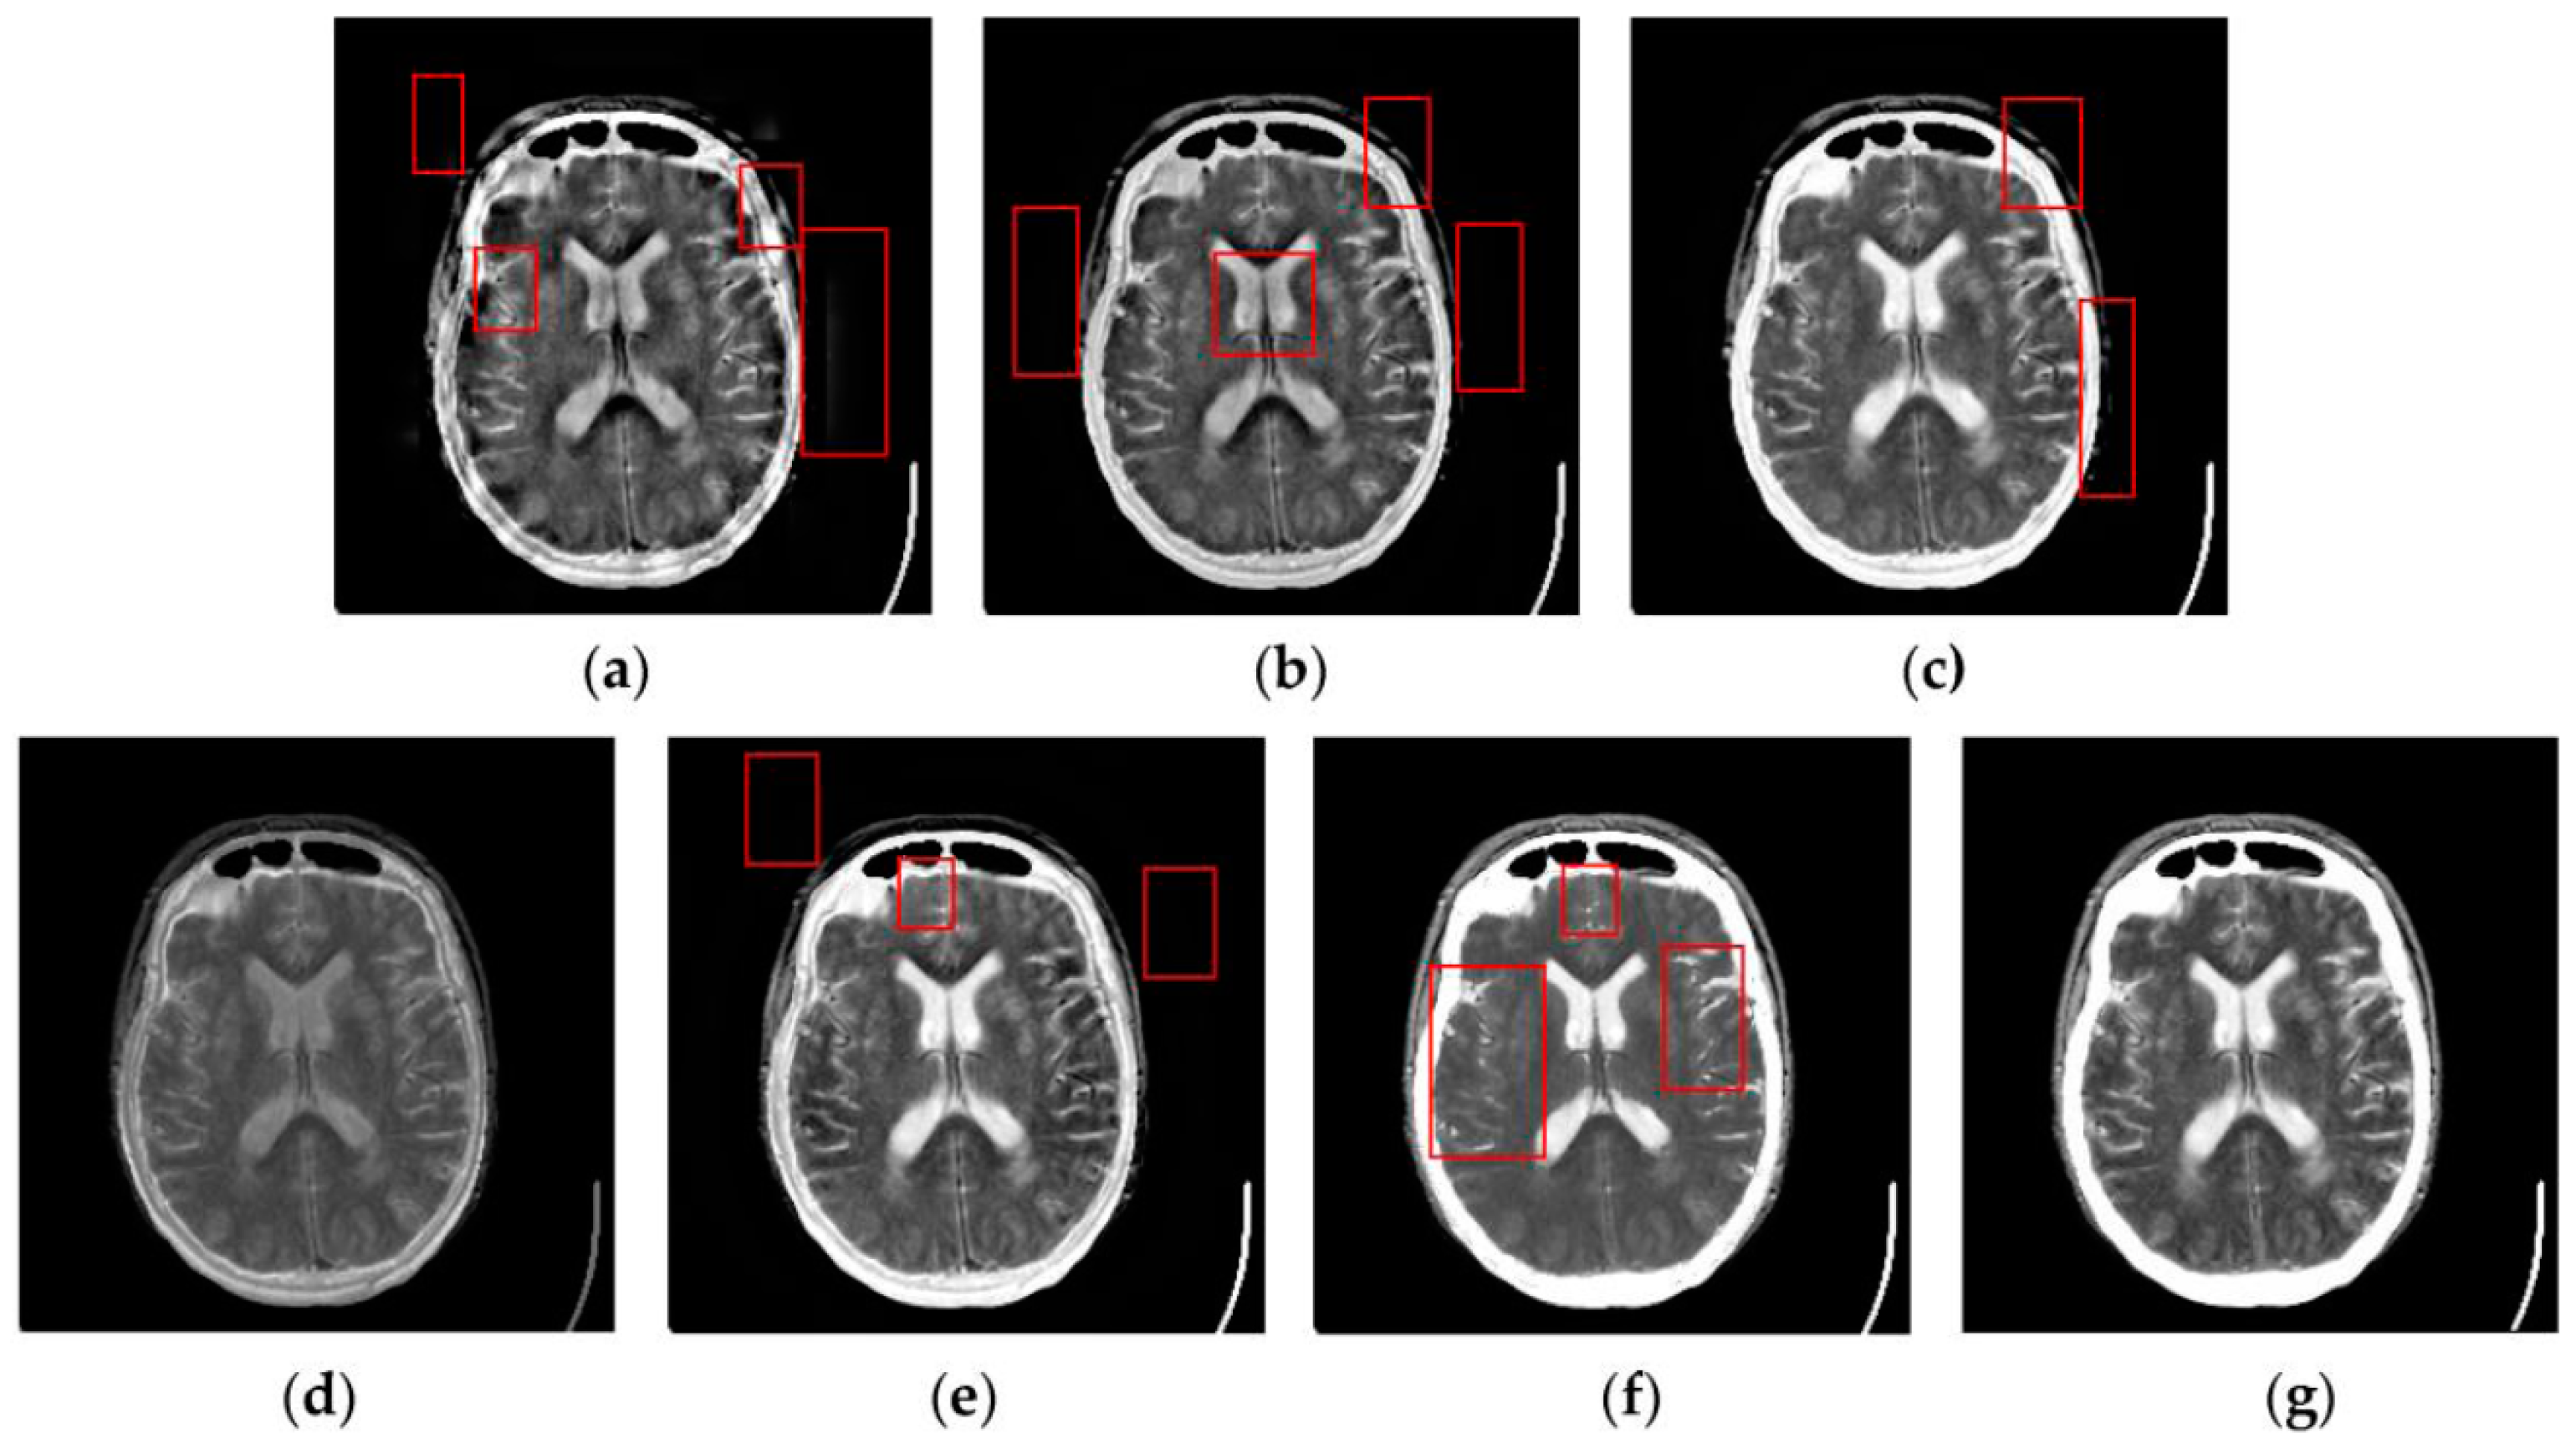

Figure 7, Figure 8, Figure 9 and Figure 10 show the fused results for the evaluated seven methods operating on such medical image pairs as Groups 1, 2, 4 and 5 shown in Figure 6, respectively. The observation from Figure 7, Figure 8 and Figure 10 shows that the DWT, NSCT and NSCT-SR methods introduce artifacts as well as false information in the fused results as indicated by the red boxes, which will greatly influence the quality of the fused images. Meanwhile, it is shown in Figure 7 and Figure 9 that the above three fusion methods cannot preserve image details well in that they produce the obvious distortion of image details marked by the red boxes in the fused results. The m-PCNN method cannot maintain the luminance of the fused results and it produces such low-contrast fused images that some important image details are difficult to identify, which is very disadvantageous for clinical diagnosis. The PCNN-NSCT method and the SCM-F method lead to loss of some important details in the source images to different extent. For example, for Groups 4 and 5, although almost all the details in the MR-T1 images can be transferred to the fused images by the PCNN-NSCT method very well, many details in the MR-T2 images have not been preserved by this method as indicated by the red boxes in the fused images shown in Figure 9e and Figure 10e. For Groups 1, 2, and 5, some image details have been seriously damaged by the SCM-F method as shown by the red boxes in Figure 7f, Figure 8f and Figure 10f.

Figure 9.

Fused results of the evaluated methods for the fourth group of source images shown in Figure 6g,h: (a) the DWT method; (b) the NSCT method; (c) the NSCT-SR method; (d) the m-PCNN method; (e) the PCNN-NSCT method; (f) the SCM-F method; and (g) the SCM-M method.

By comparison, the SCM-M method not only provides high contrast for the fused images, but also maintains important information from the various source images in the fused results effectively. In particular, the proposed method can preserve fine image details very well as shown by the red boxes in Figure 9g and Figure 10g without introducing artifacts or leading to edge blurring. The above comparisons demonstrate the superiority of the SCM-M method over other compared methods in that the fused images obtained by this method are more clear, informative, and have higher contrast.

To further verify the advantage of the proposed SCM-M method in multimodal image fusion, Figure 11 and Figure 12 show the enlarged views of fused results for all evaluated methods operating on regions of interest (ROIs) denoted by the red boxes in Groups 1 and 6 in Figure 6, respectively. Figure 13 shows the enlarged views of fused results for the proposed method, the m-PCNN method and the SCM-F method operating on ROIs denoted by the red boxes in Groups 7 and 8 shown in Figure 6. In Figure 11 and Figure 12, we can see that the SCM-M method can maintain the salient information in the source images and provide better visual perception with less loss in luminance or contrast than other compared methods. To explain this point better, some edges and regions have been chosen from Figure 11g and Figure 12g. It can be seen from Figure 11 that the SCM-M method can provide better edge preservation than all other methods as pointed by the three red arrows. Meanwhile, compared with the DWT, NSCT and NSCT-SR methods, the SCM-M method can maintain the information in the MR image shown in Figure 6f better without introducing artifacts as indicated by the two red boxes. In Figure 12, we can see that the proposed method can keep the integrity of the edge marked by the red arrow best among all evaluated methods. Likewise, as pointed by the green arrow, the edge can be preserved very well by the proposed method while it has been damaged very seriously by other methods. Besides, the sharpness of the region shown by the red box can be maintained by the proposed method better than by the compared method. Furthermore, it can be seen in Figure 13 that compared with the m-PCNN and SCM-F methods, the SCM-M method can preserve fine image details and maintain image contrast better.